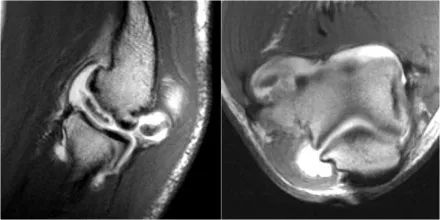

1.假的小凸起这是我们经常在冠状图像上看到。它看起来像是一个骨软骨病变,但是如果看一下矢状位图像,就会发现冠状图像穿过了髁骨的后关节部分,因此,当肘完全延伸,桡骨小头的一部分实际上是肱骨小头的后面。

在冠状视图上,我们将看到被软骨覆盖的桡骨头,并且与髁骨头的非软骨覆盖部分相对,其通常有些不规则。

2.假游离体另一个常见的发现是你在矢状图上看到的一小块脂肪,看起来像一个小游离体或软骨缺失。如果我们观察鹰嘴的关节面,可以解释这一点。鹰嘴通常有两片软骨,中间有一小块软骨,里面充满了脂肪。

3.滑膜皱襞(plica)有时可以看到关节外侧的这种结构并且是一个皱褶。它可以是突出的,几乎看起来像半月板。这是一种正常的结构,但有时它会变厚或不规则,可能是症状的原因。